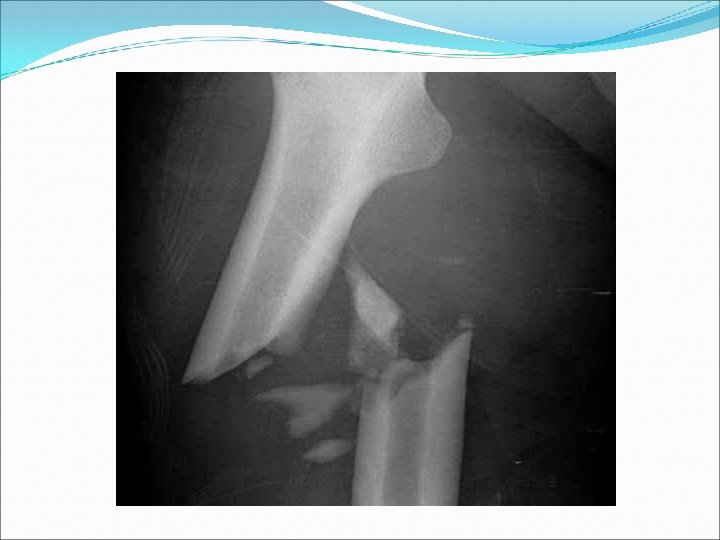

Caso 1 – Paziente coinvolto in sinistro stradale per responsabilità di terzi. All’effettuazione del controllo ortopedico a 35 giorni di distanza dal trauma veniva annotato: DENUNCIA SI o NO?